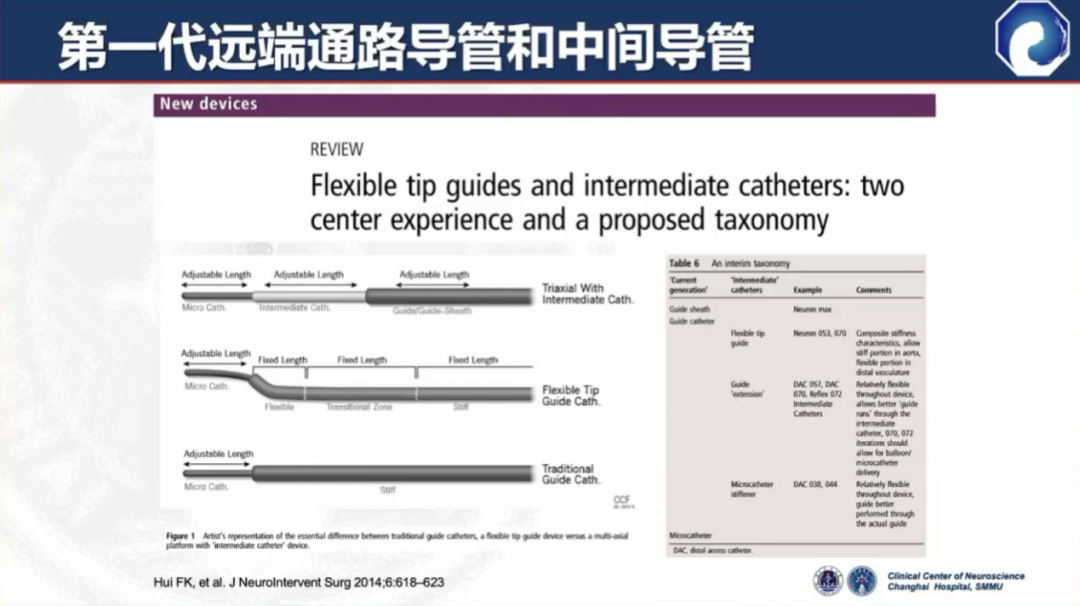

第一代远端通路导管和中间导管应运而生

代表:DAC(Stryker)、Neuron(Penumbra)

与普通导引导管相比,头端柔顺性增加,但并发症发生率仍比较高,如:夹层、血管破裂、载瘤血管闭塞等